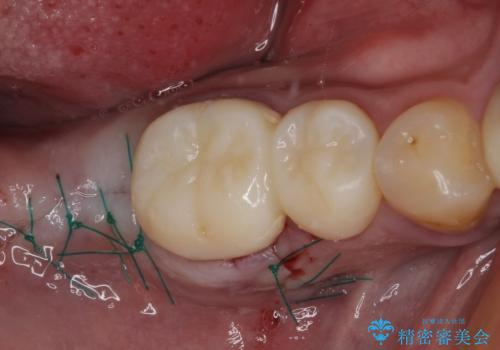

小さい修復物の銀歯が装着されている歯はセラミックインレーにて、その他はオールセラミッククラウンにて補綴治療を進めることとしました。